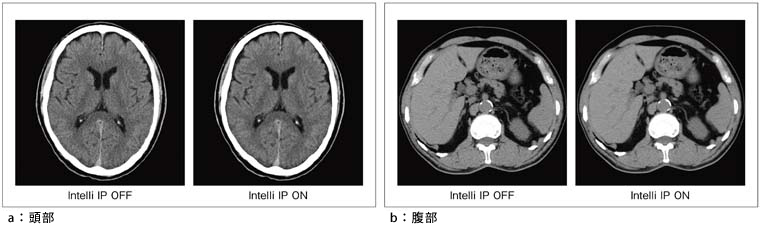

“Intelli IP(Iterative Processing)”は,従来の被ばく低減用画像フィルタと異なり,繰り返し適応型処理によって,統計的なデータの信頼性に基づいたノイズ低減処理を投影データと画像の双方に施すものであり,逐次近似法を応用してノイズ低減度,先鋭度,粒状性等のバランスを部位ごとに最適化する処理である。また,SCENARIA専用の高速演算器により,撮影中のリアルタイム処理も可能である。図4に臨床画像を示す。頭部・腹部ともに組織コントラストを保ちつつノイズを低減することができ,大幅な被ばく低減効果が期待できる。

図4 Intelli IPの効果